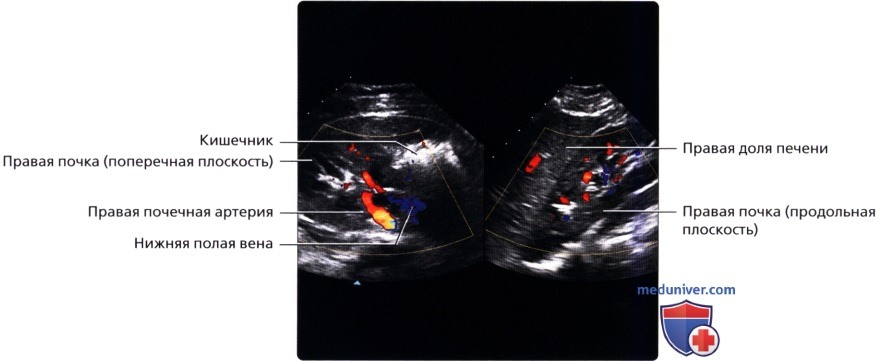

а) Анатомия почек:

б) Лучевая анатомия почки:

в) Особенности визуализации почек:

• Правая почка:

о Печень используется в качестве акустического окна

о Датчик устанавливается в подреберье или в межреберный промежуток

о Выполняйте исследование при различной глубине вдохе

о Попросите пациента немного повернуться влево, приподняв правый бок и выполняйте сканирование с боковой/заднебоковой поверхности

• Левая почка:

о Ее труднее визуализировать из-за газа в тонкой кишке и в селезеночном изгибе ободочной кишки

о Обычно левую почку проще визуализировать, используя заднебоковой эхографический доступ и попросив пациента немного повернуться вправо приподняв левый бок

о В сложных случаях полностью переверните пациента в положение лежа на правом боку, подложите подушку под его правый бок и попросите его поднять левую руку над головой:

— Для исследования верхнего полюса левой почки можно использовать селезенку как акустическое окно

• Почечные артерии:

о Места отхождения лучше всего визуализируются при сканировании по срединной линии спереди

о Правую почечную артерию обычно можно проследить от места отхождения до почки

о Для визуализации левой почечной артерии часто требуется установить датчик на заднебоковой поверхности во фронтальной проекции

• Почечные вены:

о Лучше всего визуализируются при поперечном трансабдоминальном сканировании

о Также могут быть видны при сканировании в фронтальной плоскости с заднебоковой поверхности